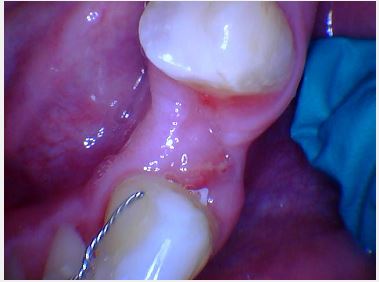

I have a patient I recently saw for an impression for an implant crown. I completed a two stage implant surgery. I didn’t note any complications at time of implant placement or uncovering.

The patient returned after three weeks for her impression. I noticed some inflammation surrounding the buccal of the healing abutment. There…

Was the healing abutment down all the way? Typically nothing should get between the healing abutment and implant if that connection is snug. I’ve seen ones where stuff gets in there with it not being down all the way.

Oral hygiene? This absolutely makes a difference when you have a fresh surgical site (even just for an uncovery) and can cause…

Hey Justin,

Thank you for sharing this case with us.

Let’s rule out some possibilities.

1. Was the healing abutment brand new? If it was brand new, was it sterile? Some docs sterilize old used healing abutments and re-use them on other patients. Unfortunately, that sometimes results in transfering debris from one patient to another, which is…